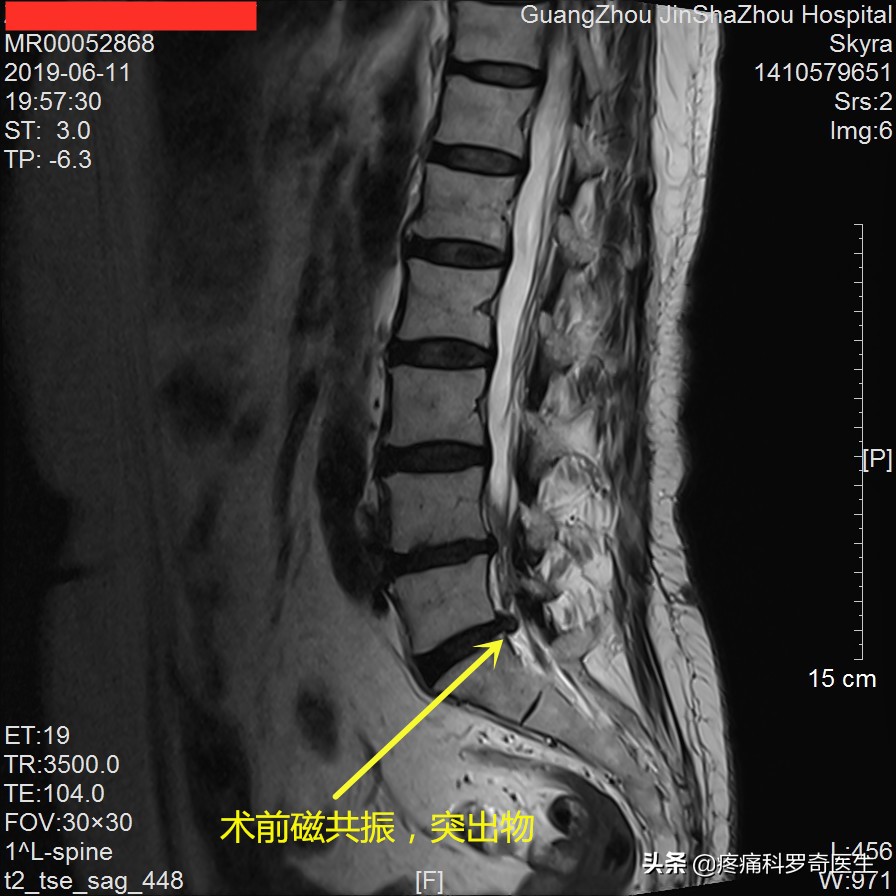

术前腰椎磁共振

从磁共振中可以看到,这个患者突出不算是特别大,但患者的下肢症状非常剧烈,而且突出物还有钙化。按照大部分专科医生的意见,这个患者至少要做椎间孔镜,拿掉突出物,拿掉钙化物,才算是最佳选择。但是通过我们对患者的检查,发现患者神经根张力很高,所以我们觉得可以不做椎间孔镜,选择创伤更小的射频消融+臭氧消融术,第一次住院做的是射频消融+臭氧消融术,第二次住院做的就是单纯的臭氧消融术。